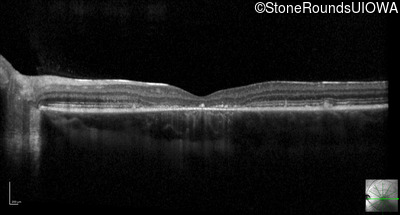

Optical Coherence Tomography - Right - 20/80 -1

Exemplar / OCT Stack

OCT Stack